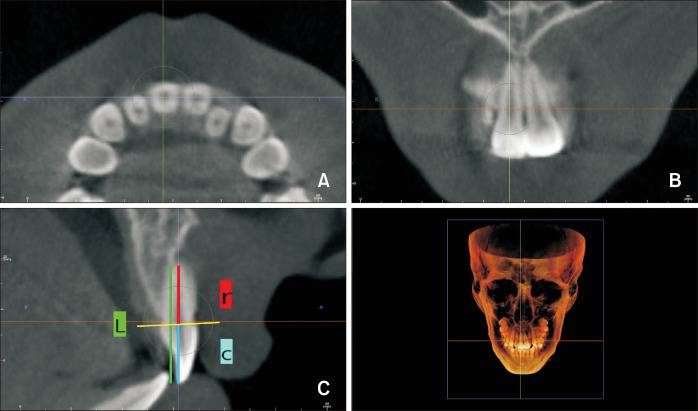

Methods: Cone-beam computed tomography images were obtained from a total of 60 patients both before expansion (T1) and 3 to 6 months after expansion (T2). Measurements taken included tooth length, root length, crown length and center of resistance. Resorption length (RL) and resorption length percentage (RLp), resorption volume (RV) and resorption volume percentage (RVp) and the amount of expansion were calculated.

Abstract Image